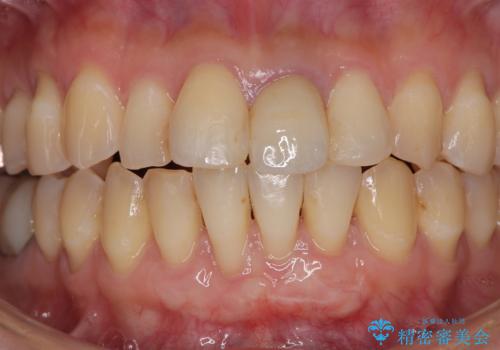

一度の処置で大幅に露出部の被覆に成功しましたが、更なる厚みと被覆を希望されて2回目の処置を行いました。

歯根部周辺の歯肉が非常に分厚くなり、今後の退縮リスクが大きく軽減されました。